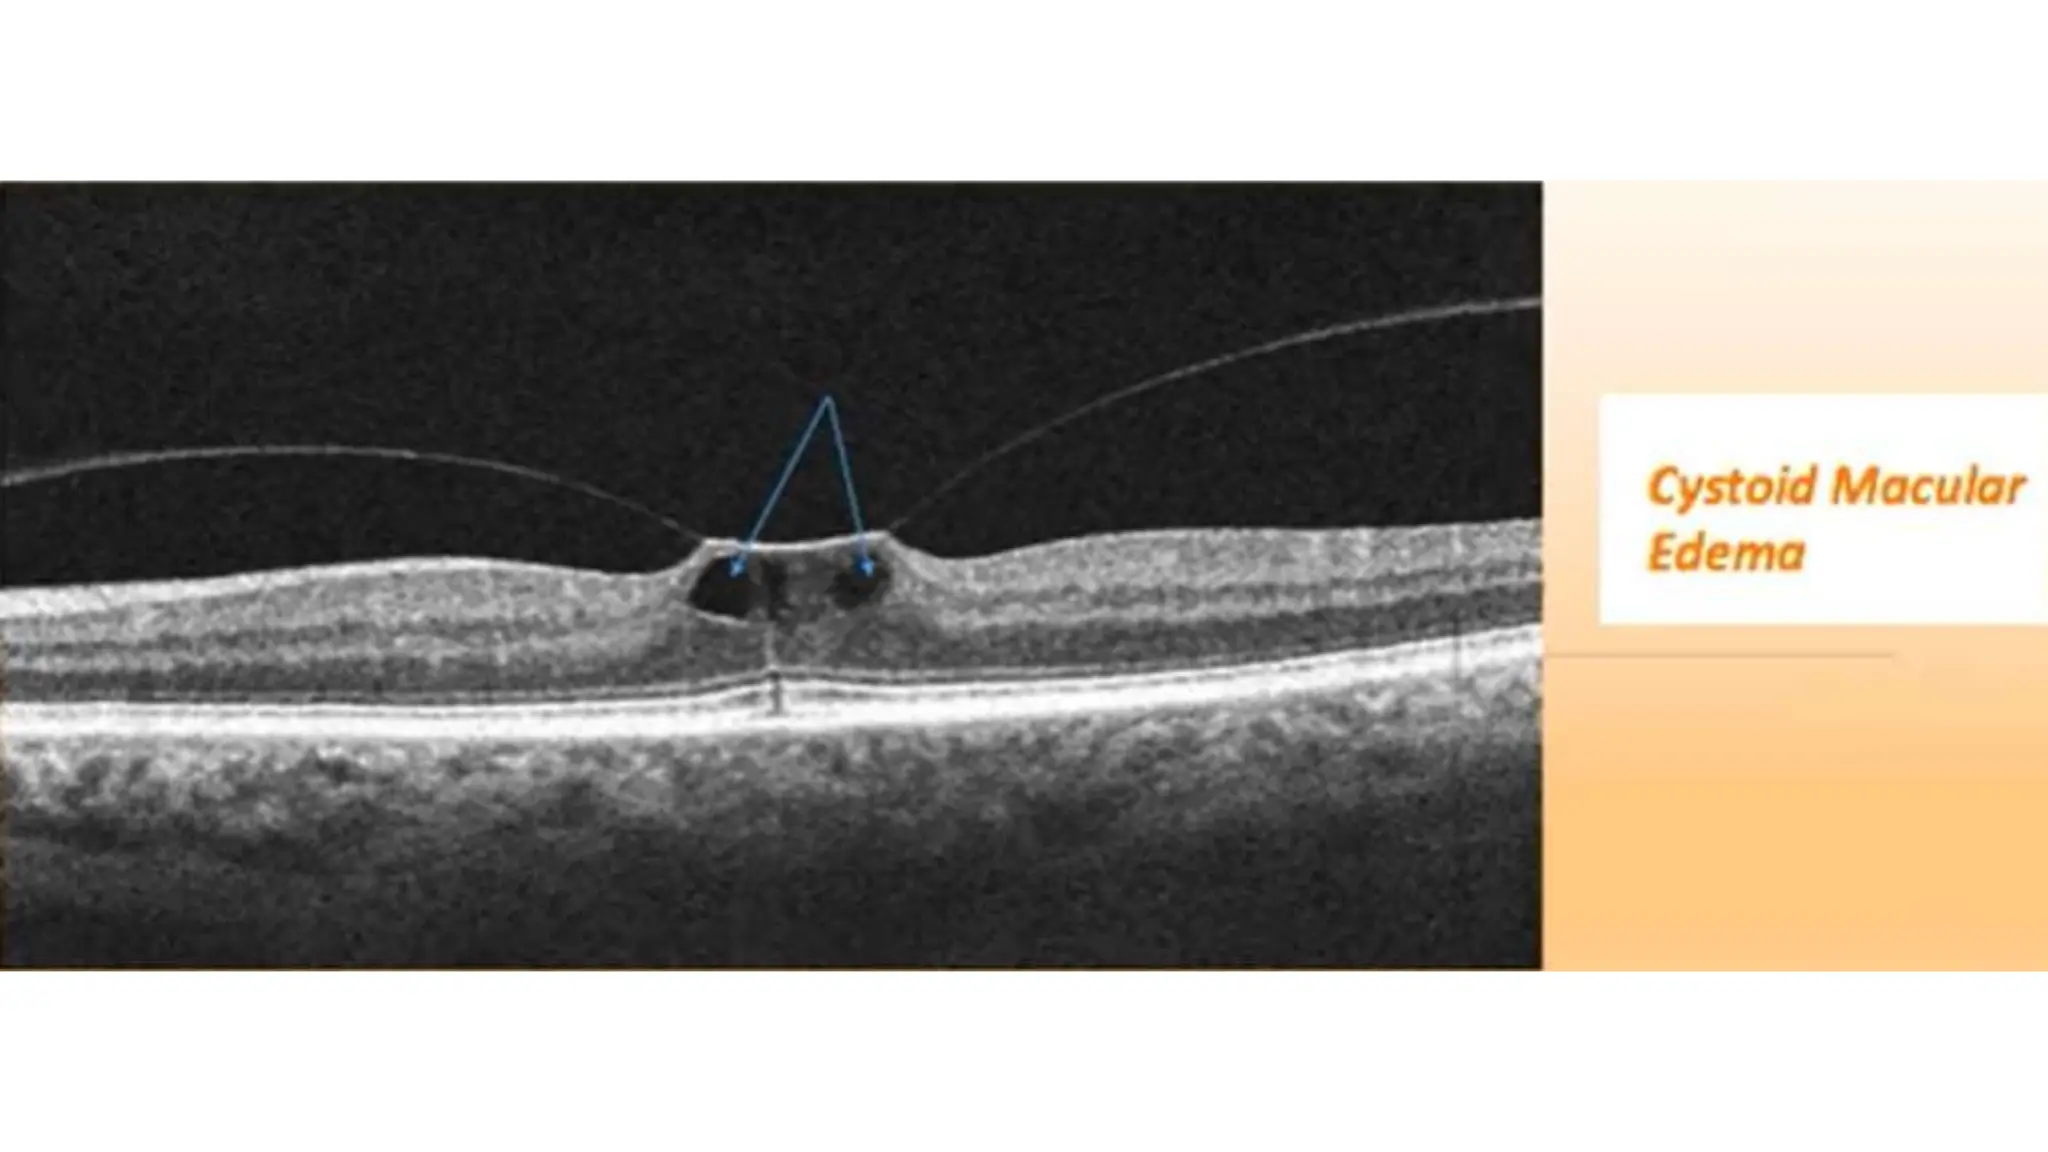

The document discusses various stages of posterior vitreous detachment (PVD) and associated ophthalmological conditions. It highlights the classification of PVD stages, including no PVD, paramacular PVD, and complete PVD, alongside related factors like traction and retinal issues. Key acronyms and terms relevant to diabetic retinopathy and retinal morphology are also mentioned.